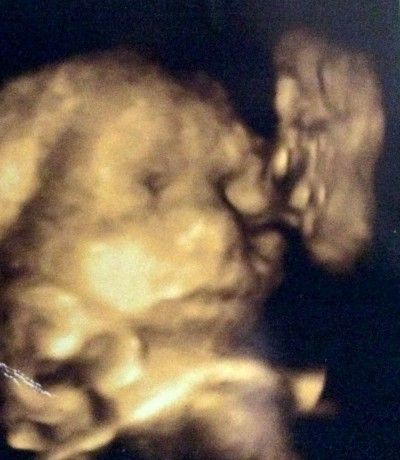

Η Τζέιντ Χόρνσμπι πήγε για να κάνει ένα 4D υπέρηχο του αγέννητου μωρού της και έμεινε έκπληκτη όταν διαπίστωσε ότι σ’ αυτόν, είχε σκιαγραφηθεί το πρόσωπο του νεκρού παππού της, να φιλά την αγέννητη κόρη της.

Όταν η έγκυος γύρισε στο σπίτι και έδειξε τις φωτογραφίες στη μητέρα της, εκείνη ήταν που τον αναγνώρισε.

«Τα μάτια, η μύτη και το στόμα ήταν τόσο ξεκάθαρα» είπε η 21χρονη και πρόσθεσε: «Είναι πραγματικά τρομακτικό. Μοιάζει ακριβώς σαν κι αυτόν, και μπορείτε να τον δείτε πιο καθαρά από την κόρη μου. Είναι σαν να είναι έτοιμος να τη φιλήσει στο μάγουλο».